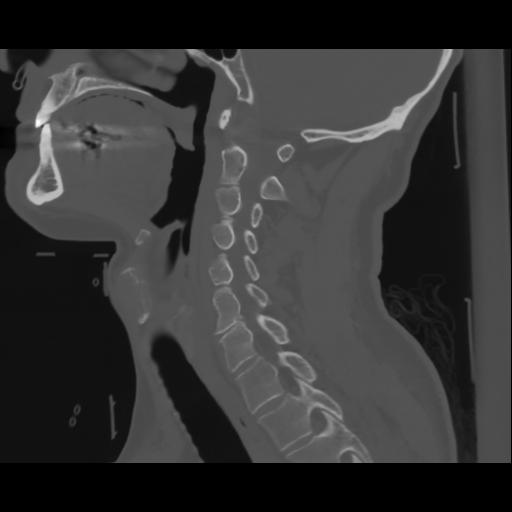

14 P.BLANDAS,,Sagittal,2.000,P.BLANDAS,Sagittal,